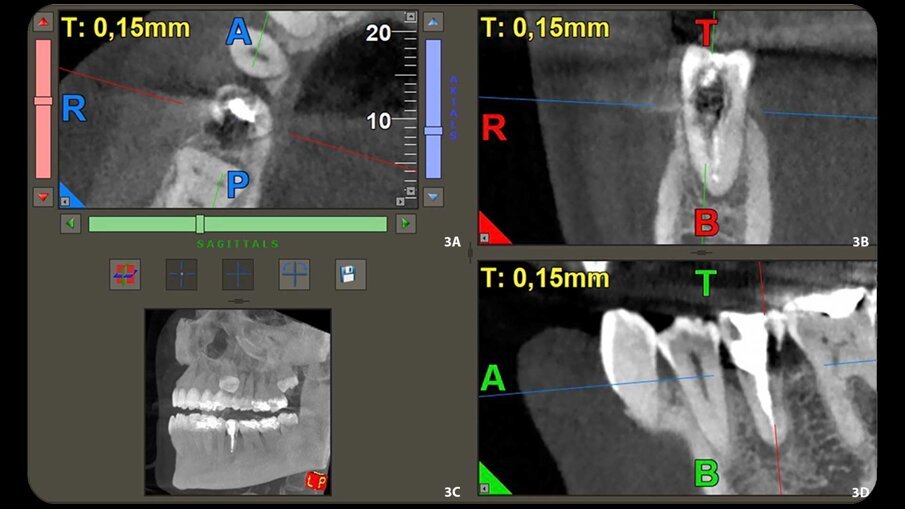

L’esame radiografico ha mostrato radiolucenza periapicale e una lesione radiolucente nella zona cervicale del dente (Figg. 1, 2). Per determinare l’estensione e la profondità della lesione, è stata eseguita una scansione CBCT (Figg. 3a-3d). Sulla base delle immagini CBCT e delle ricostruzioni 3D, è stata individuata una diagnosi di riassorbimento invasivo extracanalare (ECIR) di classe III di Heithersay in un dente trattato endodonticamente con parodontite apicale sintomatica. Il paziente è stato informato della diagnosi, delle alternative del piano di trattamento e della prognosi del caso. L’ECIR è una forma di riassorbimento della radice cervicale esterna e rappresenta ancora un enigma per gli endodontisti per quanto riguarda la sua natura e le sue cause. In questa circostanza, potrebbe essere stato dovuto dalle forze generate dal trattamento ortodontico o da precedenti trattamenti parodontali, poiché il dente 45 era stato precedentemente diagnosticato con parodontite cronica sintomatica. Il difetto di riassorbimento causato dall’ECIR viene trattato, come proposto da Heithersay, utilizzando una nuova alternativa terapeutica, quale l’estrusione chirurgica intenzionale e la chirurgia periapicale1. Heithersay ha classificato l’ECIR in quattro tipi clinici. Nella classe I e II, la percentuale di successo del trattamento è generalmente del 100%, ma la percentuale di successo del trattamento scende al 77% nella classe III e al 12% nella classe IV. Quanto più avanzato è il riassorbimento, tanto peggiore è la prognosi e tanto più complesso il trattamento1.

Figg. 3a-3d - Ricostruzione 3D della sezione assiale che mostra l’estensione in direzione mesiale-distale (a). Ricostruzione 3D della sezione sagittale che mostra l’estensione della lesione, direzione bucco-palatale (b). Sezione coronale della CBCT che mostra l’estensione della lesione periapicale e il difetto di riassorbimento (c). Scansione CBCT (d).

La CBCT è uno strumento utile in endodonzia, utilizzato per valutare l’entità del difetto di riassorbimento cervicale esterno, per rilevare e classificare la parodontite apicale e per valutare i riferimenti anatomici con maggiore precisione. Diversi autori hanno dimostrato che la CBCT è molto utile nella diagnosi di questo tipo di riassorbimento2-4. Nel caso clinico presentato, sono state osservate una lesione apicale e un ECIR, e la CBCT è stata utilizzata per osservare la dimensione della lesione periapicale e la dimensione e la localizzazione del difetto di riassorbimento nei tre livelli spaziali. Diversi fattori intervengono nella guarigione della parodontite apicale dopo l’intervento chirurgico periapicale, come la profondità della retro-preparazione apicale, che deve essere di almeno 3 mm, il materiale scelto per la retro-otturazione e il tempo di follow-up. Ulteriori scansioni CBCT sono state necessarie in questo caso per confermare la completa guarigione della lesione. L’estrusione chirurgica intenzionale è stata tentata con lo stesso trattamento chirurgico minimamente invasivo5, 6. Il tessuto di granulazione del difetto di riassorbimento è stato rimosso e l’area è stata sigillata con acido tricloroacetico al 90% e riempita con un cemento ionomero nano-ibrido di resina idrofila a doppia polimerizzazione (Geristore, DenMat; Figg. 4a, 4b). La chirurgia apicale è stata poi eseguita a 3 mm utilizzando le punte ultrasoniche del kit di chirurgia apicale EndoSuccess (ACTEON). La retro-otturazione è stata eseguita con un cemento minerale a triossido aggregato (CeraPutty, Meta Biomed), e il dente è stato riposizionato all’interno dell’alveolo, splittato con filo intrecciato semiflessibile per quattro settimane (Figg. 5a-5d)7, 8. Dopo sei mesi, è stata eseguita un’altra scansione CBCT per valutare la guarigione. Si è osservata una risoluzione quasi completa della lesione periapicale (Fig. 6). Anche la situazione intraorale sembrava buona, e non c’erano segni di patologia apicale sulla radiografia periapicale, che ha anche mostrato la guarigione quasi completa (Fig. 7). Il dente è rimasto asintomatico.